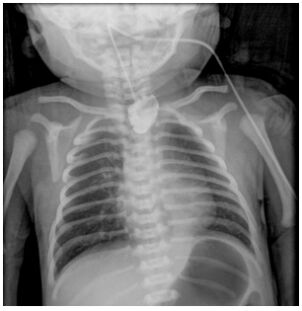

複選題44.一名33週的早產兒,出生後生命徵象穩定,但在第一次餵奶時發現有咳嗽、嗆到、發紺的狀況,且伴隨著大量口水流出;當試著置入胃管時,發現無法放至胃部,因此新生兒科醫師安排食道鋇劑攝影如圖。針對上述情況,下列相關敘述何者錯誤?

(A)該患兒必定伴隨著食道氣管瘻管(tracheoesophageal fistula) (B)該患兒很可能身體有其他的異常,因此一定要再檢查其他器官系統有無異常(C)該患兒之疾病以Gross type C最常見(D)若沒有其他更緊急的狀況,患兒應儘速接受手術治療 .